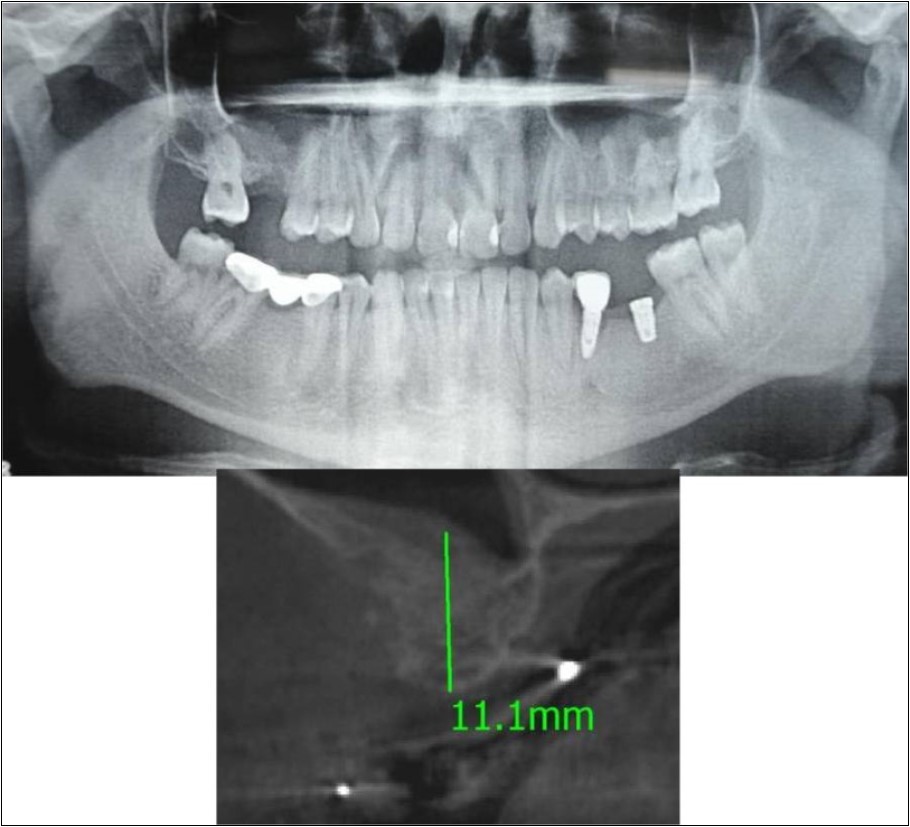

Patient underwent the procedure of direct sinus elevation using sinus lateral approach kit. After crestal and vertical release incisions, muco-periosteal flap was raised to expose the buttress region. A bony window of 1cm diameter was created; sinus lining identified and elevated up to receive calcium phosphosilicate as graft material and closure was achieved under local anaesthesia and strict aseptic protocols. Implant placement was planned to be carried-out after a period of 6 months to allow for the consolidation for graft and naive bone formation. At the end of 6 months, a repeat CBCT scan was advised to evaluate the increase in bone height. (Figure 17a,b, pre-treatment; Figure 18a,b, post-treatment)

Figure 17.a,b. Pre-treatment OPG and cross section of CBCT showing residual alveolar bone height for Case No.6;

Figure 18.(a,b) Post-treatment OPG and cross section of CBCT showing residual alveolar bone height for Case No.6;